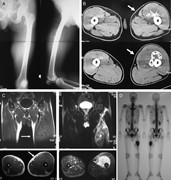

Intercalary endoprosthesis for salvage of failed intraoperative extracorporeal autogeneous irradiated bone grafting (IORBG) reconstruction

Kenichiro Hamada and others

Journal of Surgical Case Reports, Volume 2014, Issue 3, March 2014, rju014, https://doi.org/10.1093/jscr/rju014